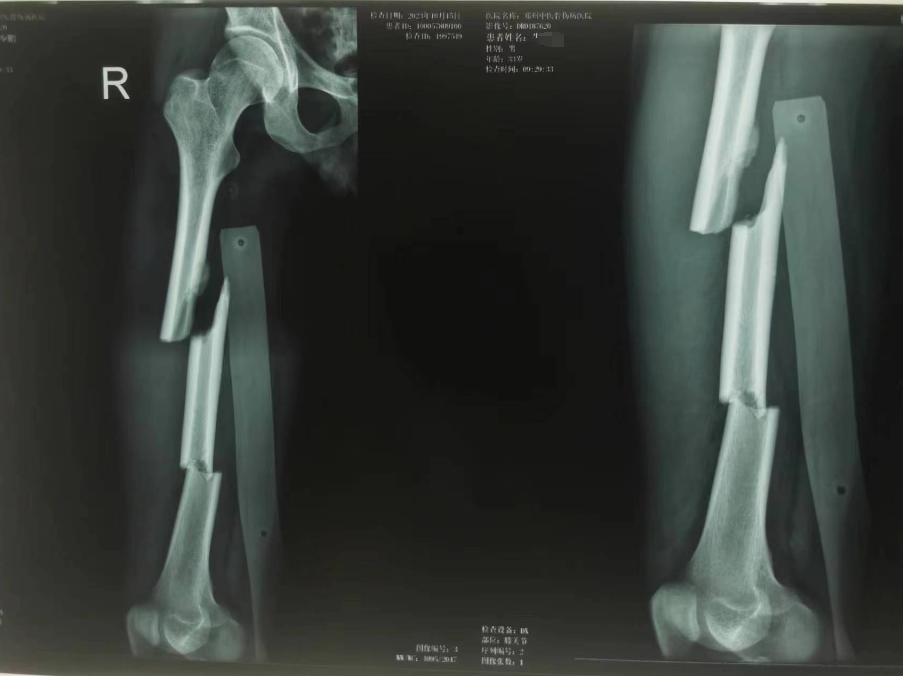

调度员种莎莎立即上报 120 中心,接到 120 中心出车指令,迅速出诊、上车、前往患者救治地点。到达现场后,出诊组给予右下肢夹板固定,建静脉通路,心电监护,快速转至医院进一步治疗。完善相关检查后,以「右股骨干骨折」为诊断收住入院。

入院后,结合相关检查,为患者行「右股骨干骨折切开复位内固定、同种异体骨植骨术」,术中通过 x 线透视复查,见骨折复位恢复正常。通过院前院内的共同努力,在急诊外科未智慧主任、陈伟医生和护理人员的精心照护下,患者已经能够掌握一些康复功能锻炼,并于 10 月 26 日康复出院。